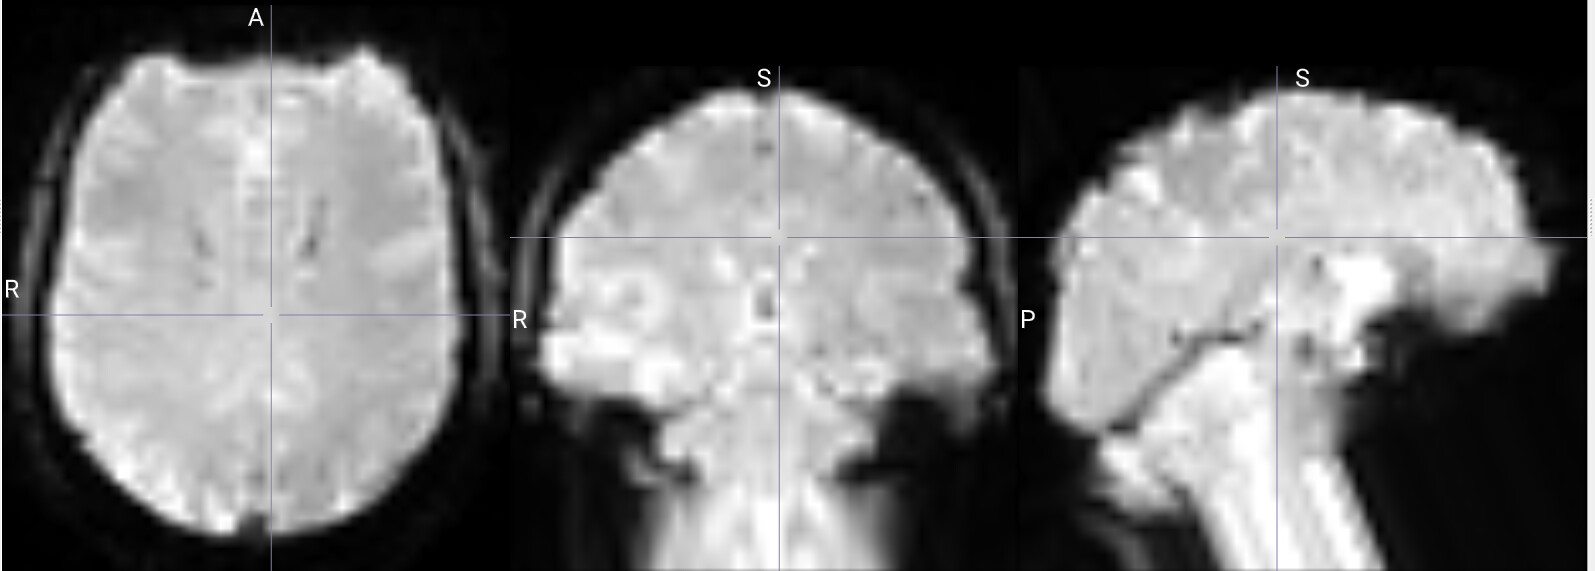

I am running fmriprep for the first time, and my preproc_bold.nii files have a weird distortion extending from the cerebellum for a few slices, it is basically a copy of what seems like the final slice, extending anteriorly.

The copied slices are overlapping with the superior slices, likely messing with the voxels.

images showing how it extends anteriorly: